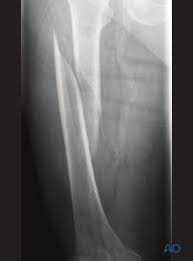

Spiral fracture - Definition

The fracture spirals around the bone

Spiral fracture - Cause

Caused by a twisting force

Spiral fracture